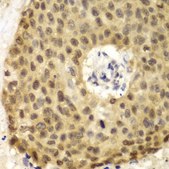

Application:

immunohistochemistry: 1:50-1:200, western blot: 1:500-1:2000